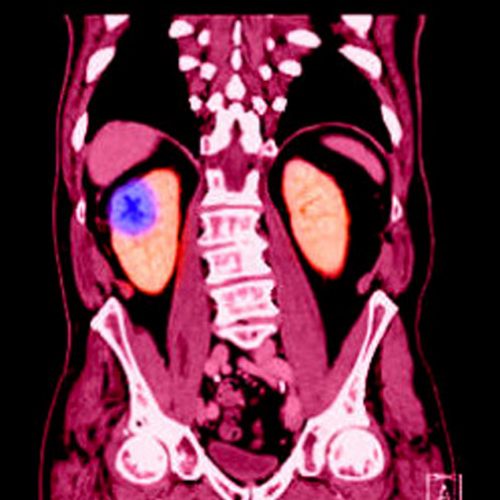

SMIL moves quickly to add NETSPOT® for NETs diagnostic imaging November 10, 2017 By Nishant Verma, MD